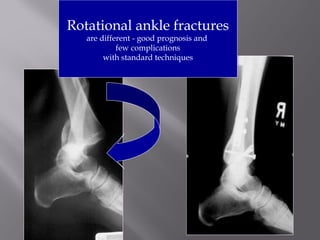

Rotational ankle fractures

are different - good prognosis and

few complications

with standard techniques